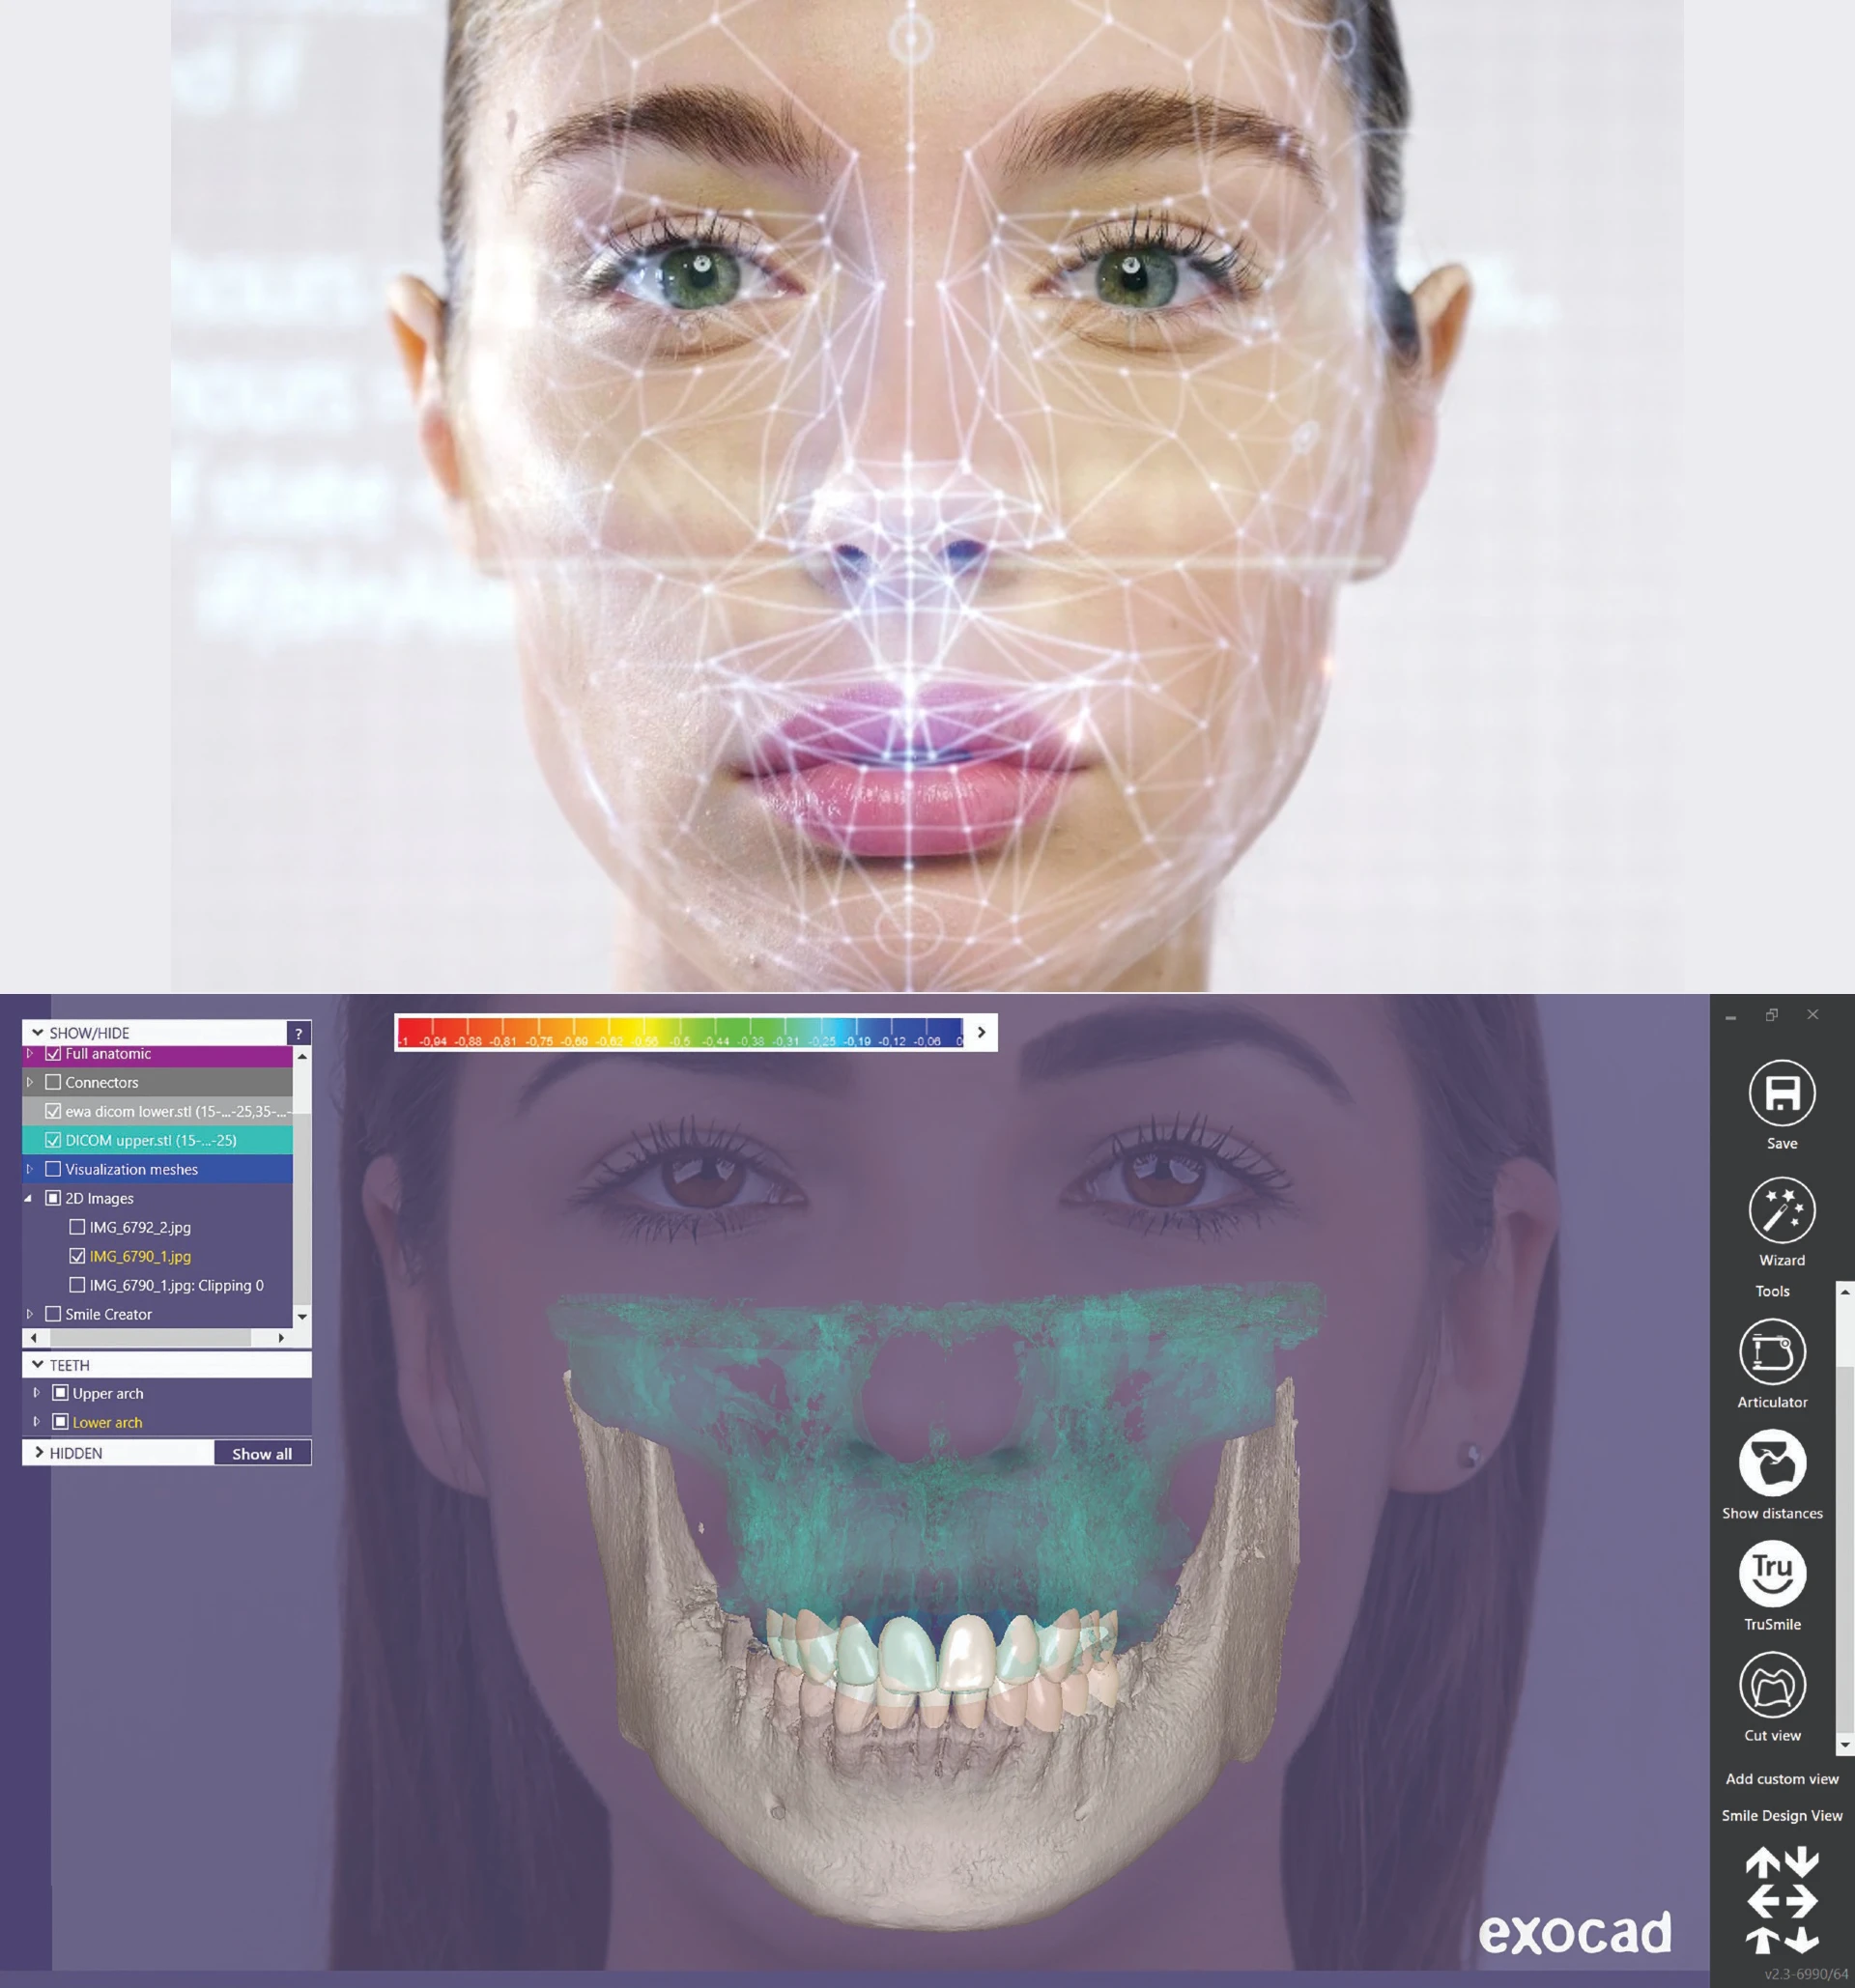

At the heart of our commitment to excellence lies photogrammetry technology, a revolutionary dental imaging system that sets new standards in precision and patient care.

What sets photogrammetry technology apart from other imaging systems? Imagine a dental tool that provides a comprehensive view of your oral health with unparalleled clarity and detail. That's exactly what photogrammetry delivers. Using state-of-the-art technology, it captures high-definition images of your teeth, gums, and jaw from every angle, allowing our skilled professionals to plan and execute treatments with unmatched accuracy.

Whether you're considering dental implants to replace missing teeth or seeking solutions for complex oral health issues, photogrammetry technology empowers our team to tailor treatment plans to your unique needs. With its 4D capabilities, it goes beyond traditional imaging systems, capturing not just static images but dynamic movements within your mouth, ensuring optimal results and long-lasting satisfaction.

Say goodbye to guesswork and hello to precision dentistry with photogrammetry technology.

Using a facial scanner for denture fabrication offers several benefits. By capturing accurate digital images of a patient's face, teeth, and gums, the scanner can assist in creating dentures that are comfortable, functional, and aesthetically pleasing.

Here are some of the specific benefits of using a facial scanner for denture fabrication:

Overall, using a facial scanner for denture fabrication can lead to more accurate, aesthetically pleasing, and functional dentures that are more comfortable for the patient. This technology can also help to reduce the amount of time required for denture fabrication.